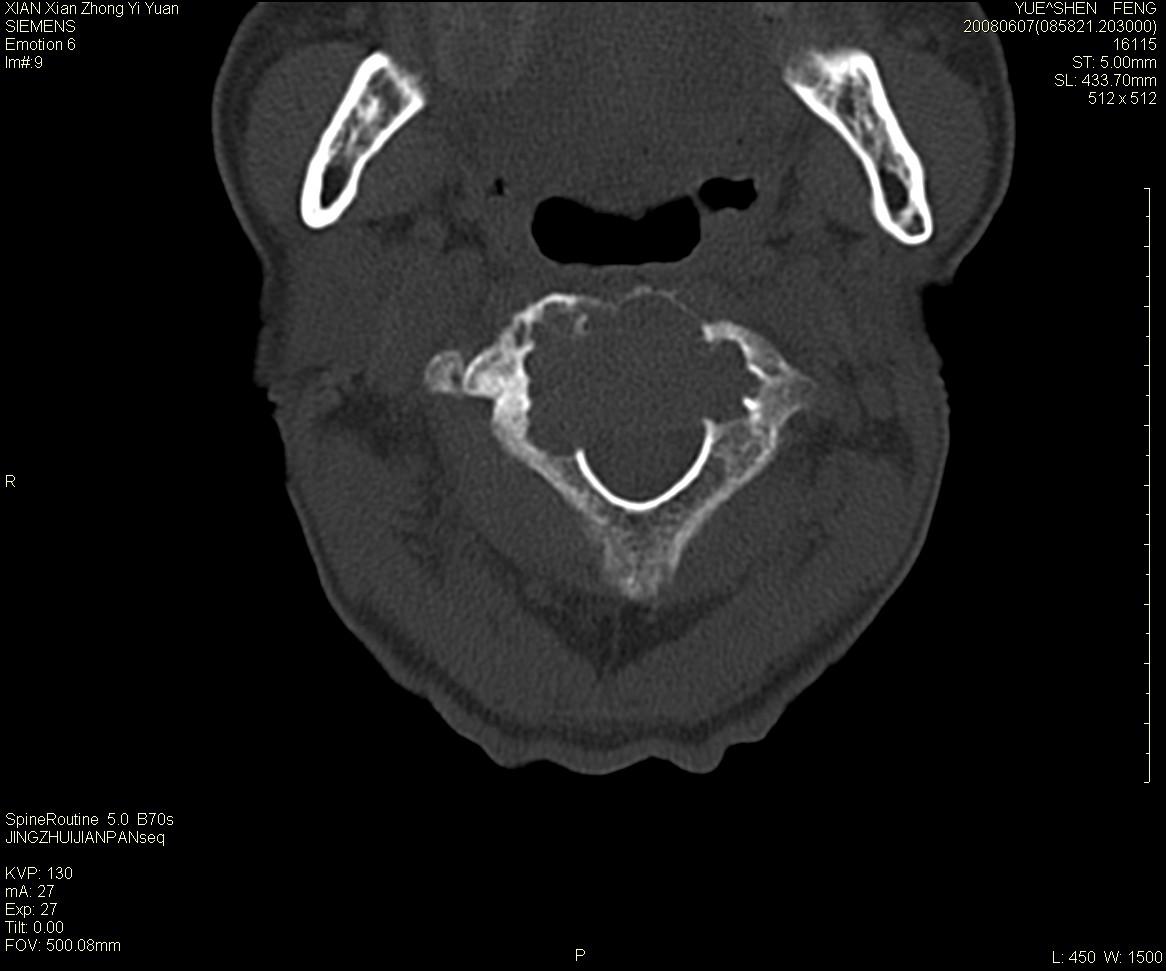

标题: CT13889:M72,颈部疼痛两年,近来加重。 [打印本页]

标题: CT13889:M72,颈部疼痛两年,近来加重。

枢椎囊状膨胀性改变,边缘锐利,周围无软组织肿块,考虑骨巨细胞瘤可能。转移瘤破坏膨胀性改变较轻。

作者: XIANXIANZHONGYI    时间: 2008-6-9 18:06

考虑浆细胞瘤

依据:

1 老年男性,颈部疼痛两年余。

2 ct:枢椎椎体显示膨胀性溶骨性骨质破坏,受损区域较大,边界清晰,其中似可见有小囊状结构,并残存有少量的骨小梁。病变与正常骨组织之间有一狭窄的分界区。受损部位部分边缘显示轻度骨质硬化。病灶突破骨皮质并在椎管形成软组织肿块影。

影像学检查:骨骼x线表现为单一部位的溶骨性改变,受损区域较大,边界清晰,其中可见有小囊状结构,少数可残存有少量的骨小梁。病变与正常骨组织之间有一狭窄的分界区。部分患者可见到病理性骨折,少数表现为受损部位的骨质硬化。ct和磁共振(mri)检查可以更加清晰地显示病损范围和性质以及周围软组织情况,并可能发现x线未显示的病灶以及更准确地判断骨髓是否受累。骨孤立性浆细胞瘤的ct和mri表现为扩张性溶骨性改变,骨质的破坏区完全被软组织肿块所代替,骨质膨胀,边界清晰,常突破骨皮质并在附近形成软组织肿块影。脊柱受累还可深入到锥管压迫神经束或神经根。